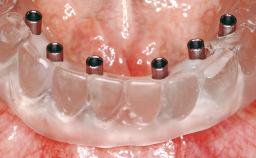

Immediate Loading of Two Implants in the Mandible and Final Restoration with a Bar-Supported RDP

A 56-year-old female patient was referred to the clinic because of retention problems with her mandibular denture. She had been completely edentulous for more than 33 years and wore her sixth set of complete conventional dentures, which had been delivered 5 years previously. An oral surgeon had performed a vestibuloplasty in the interforaminal region of the mandible with a piece of skin tissue 12 years earlier. The panoramic radiograph and lateral cephalometric radiograph exhibited the hypotrophy of the inferior alveolar process. The mandible was a Cawood class VI,and the height of the mandible in the interforaminal zone was 15 mm.

# of Implants | 2 |